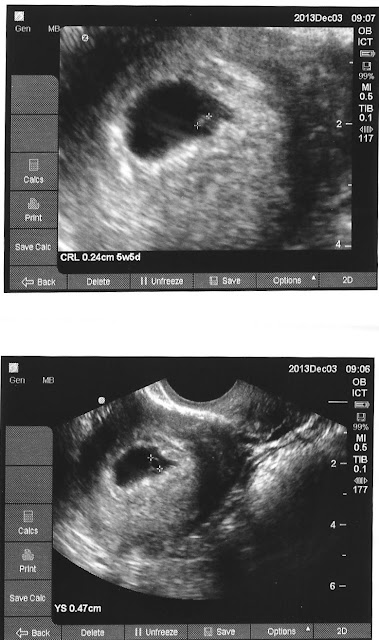

Good news is that I have at least one baby in utero. Saunders said there could very well be another one in there but she can't see it just yet. I know they can develop at different rates considering the two embryos weren't genetically related to one another.

The sac with fetal pole was measuring 5 wk 5 days Yolk sac was .47 cm, CRL 0.24 cm. Heart could be seen flickering away. Dr. Saunders didn't see it when I saw it flickering. She went back to it and saw it the second time around. Yup J and I have some real hope. I just need to keep the stress down and this pregnancy might just make it.